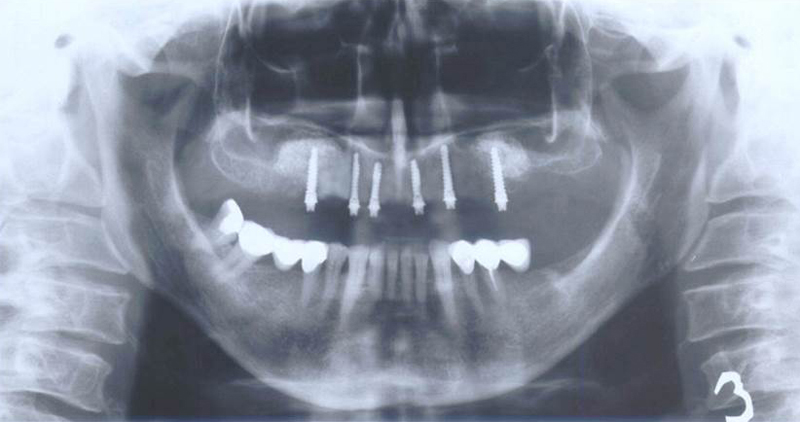

Sinus lift

Nejčastější oblastí pro doplnění kosti je čeleni dutina horní čelisti.

Tento výkon se nazývá sinus lift - aplikace kostního granulátu do čelistní dutiny

Při ztrátě molárů a premolárů v horní čelisti a jejich náhradě implantáty se často setkáváme s nedostatečnou vertikální nabídkou kosti pod čelistní dutinou, často doprovázenou i nedostatečnou horizontální nabídkou a sníženou kvalitou kosti

(v oblasti 2. premoláru v 50%, v oblasti moláru až v 80% případů nedostatečná kostní nabídka)

Od roku 1985 je tento problém řešen augmentační operací nazývanou sinus lift.

Jedná se o vyzvednutí membrány, která čelistní dutinu vystýlá, pod vyzvednutou membránou vznikne kapsa, kam se umístí augmentační materiál, do kterého se zavedou implantáty.

Vhojení implantátů se při této operaci prodlužuje na 6-12 měsíců.